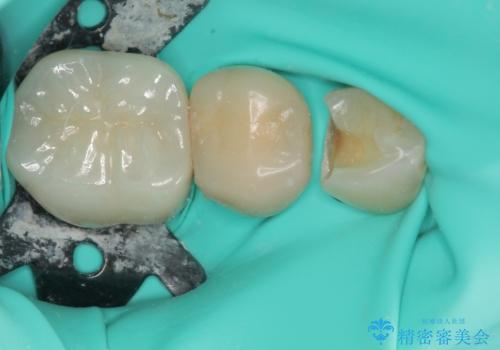

検診で見つかった齲蝕のセラミックインレー修復

- 検診で初期の齲蝕が見つかった患者様です。

これ以上神経の治療や被せものになりたくないため、初期のうちにしっかりとした治療をしたいとのことでした。

齲蝕をしっかりと除去して、精度の高いシリコーンによる型どりを行いセラミックインレーで修復しました。

唾液による接着阻害を防ぐために、ラバーダム防湿を行っています。